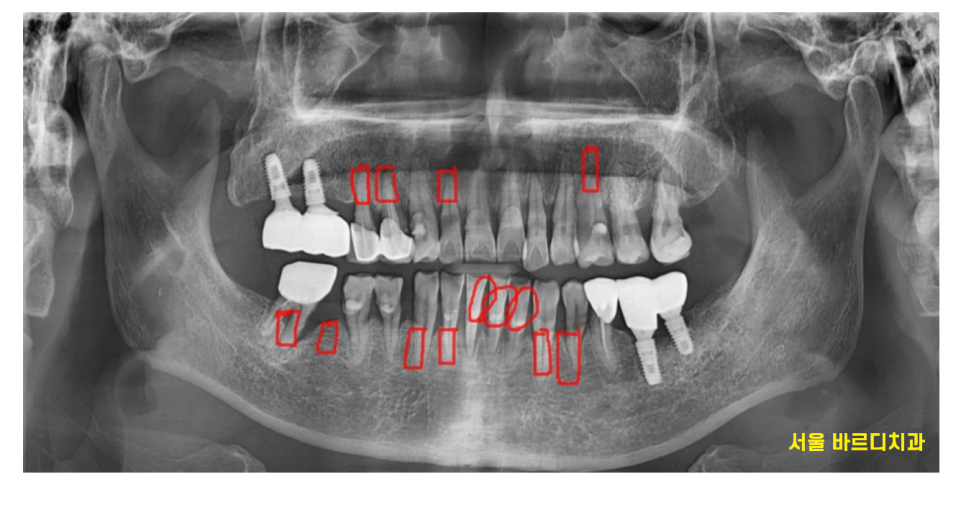

1-2개 치아가 아닌

위아래 치아 흔들림이 있을 경우에는

잇몸뼈가 얼마나 내려가 있느냐에 따라

치아 수명을 평가하게 됩니다.

최대한 치아를 많이 살리고 싶어서

치아 1개씩 사진을 찍어

평가해보았습니다.

240425

치료를 해도 오래 못쓸꺼같은 치아들은 뽑고

강일동 임플란트로 상담드렸습니다.

윗니 4개 임플란트

아랫니 6개 치아

총 10개의 강일동 임플란트 치료를 하셔야했습니다.